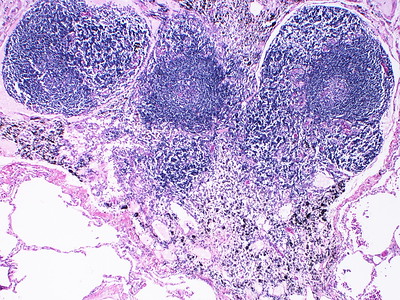

带有生殖中心的淋巴卵泡,即SCP-8683活动的部分,染成深紫色

描述:SCP-8683是负责脊椎动物适应性免疫的智慧体。在免疫反应中,它会重构生殖中心内B细胞的DNA1产生针对遇到的病原体和毒素的特异性抗体。